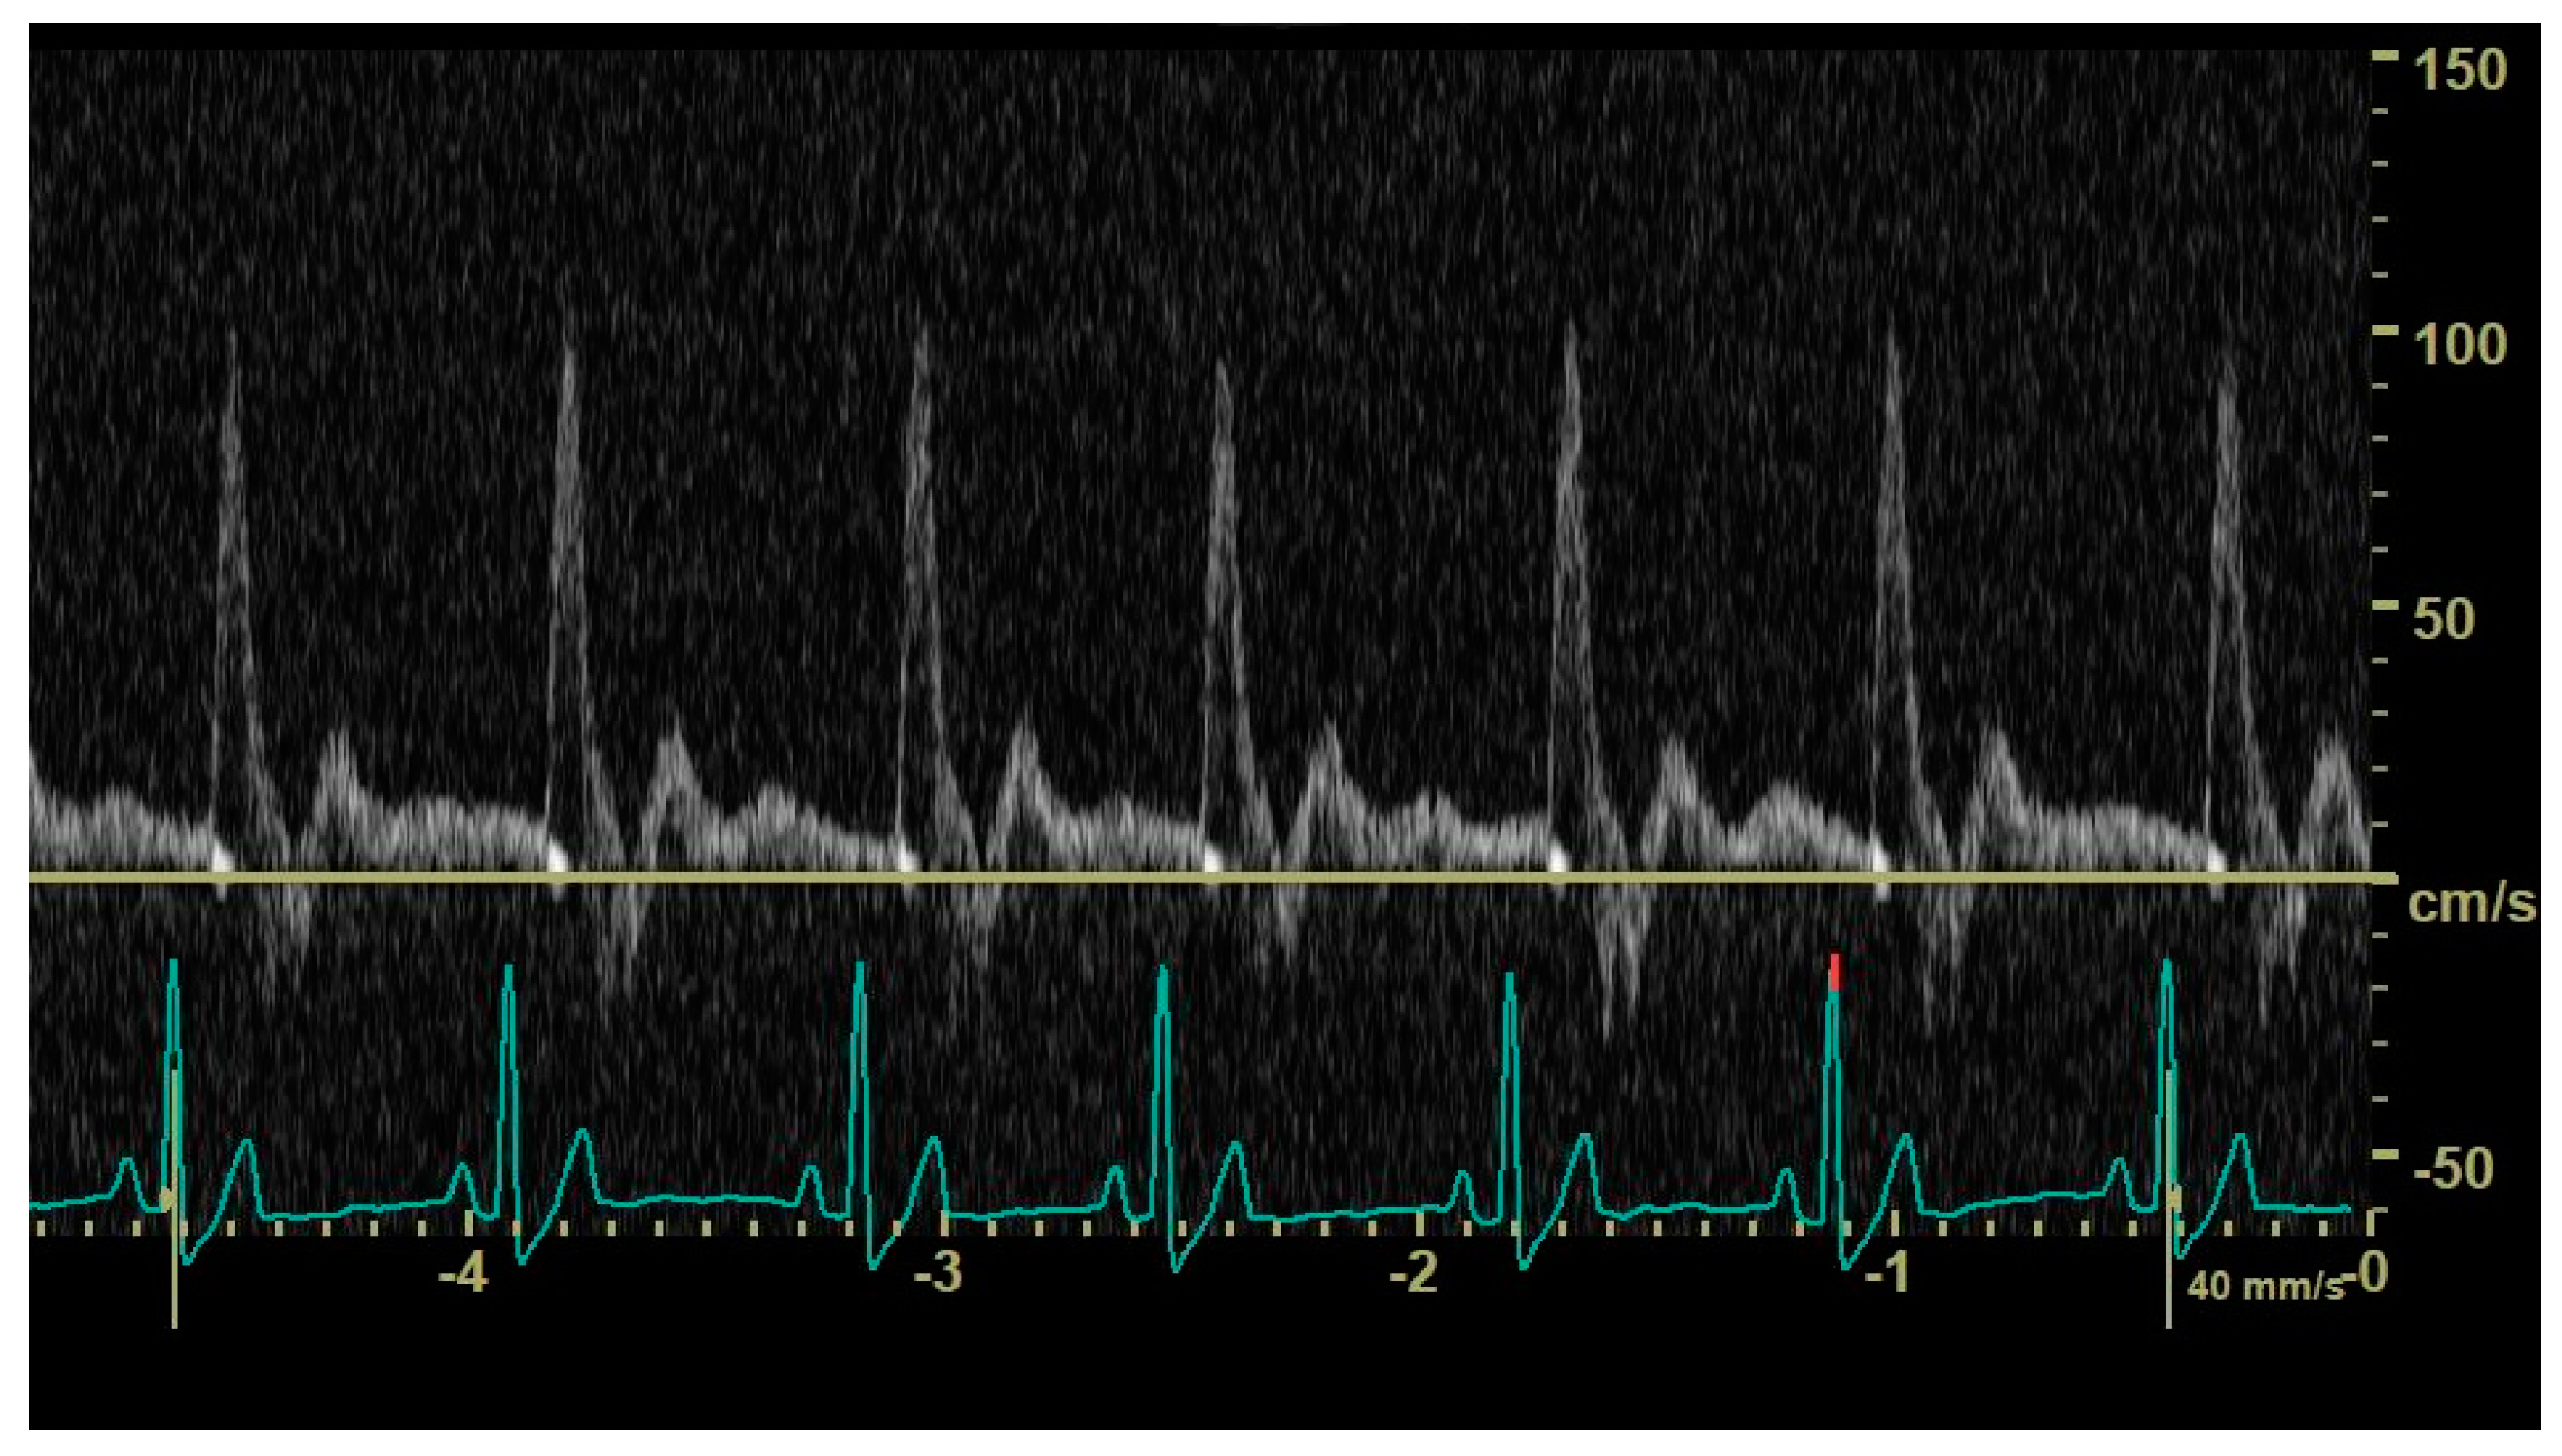

2.3. Doppler Ultrasonographic Assessment of Abdominal Aortic Flow

3.2. Echocardiographic Findings and Abdominal Aortic Flow Pattern